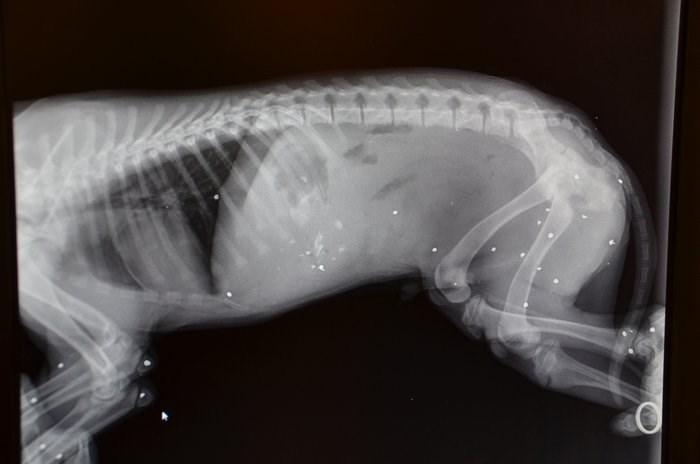

Αμέσως ενημερώθηκε ο Σύλλογος και έσπευσε στο σημείο μαζί με την Ασφάλεια Άργους, όπου και μετέφεραν το μικρό κουτάβι στον κτηνίατρο. Έπειτα από ακτινογραφίες, διαπιστώθηκαν πάνω από 25 θραύσματα μέσα στο κορμάκι του.